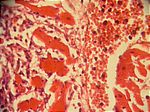

bakt. Myokarditis mit Abszedierung, HE